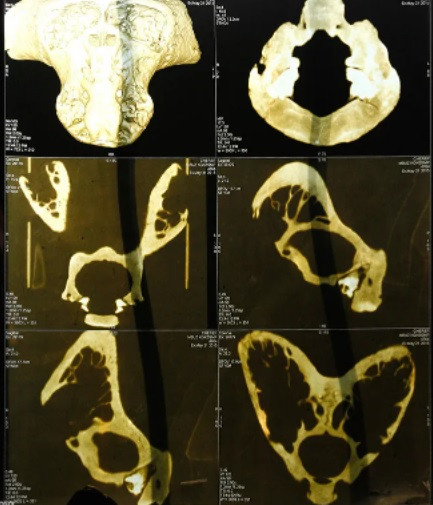

Việc tìm thấy chiếc hòm chứa 2 hộp sọ bí ẩn trên khiến giới chuyên gia vô cùng bất ngờ và tò mò. Nguyên do là bởi những hộp sọ này không có vòm sọ và hàm.

Hốc mắt to bất thường và có nhiều đặc điểm trên khuôn mặt không giống con người. Thậm chí, trên hộp sọ còn có 2 chiếc sừng mọc tách biệt nhau.

Những đặc điểm trên khiến giới chuyên gia cho rằng đó không phải là hộp sọ của con người. Từ đây, một giả thuyết cho rằng, 2 hộp sọ đó có khả năng thuộc về người ngoài hành tinh.